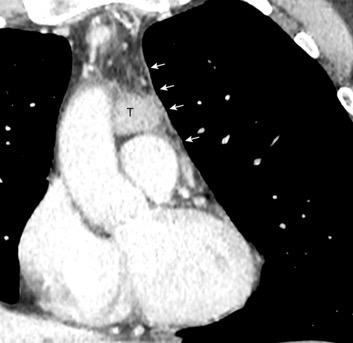

102. HEMATOMA MEDIASTÍNICO.

Hematoma retroesternal y pericárdico en cirugía de válvula mitral. Migración de suturas

Boiselle P.M.et al. Wandering wires: frequency of sternal wire abnormalities in patients with sternal dehiscence. AJR 1999;